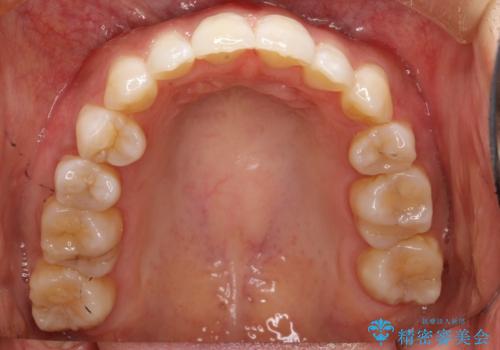

前歯の叢生があり、上下の前歯が接触していない開咬という状態でした。

左側の上下の前から4番目の歯を抜歯して、矯正することとしました。